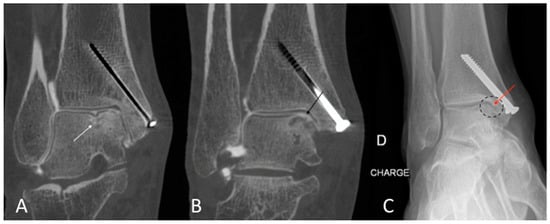

Figure 7. CBCT-A of right ankle in coronal (A,B) planes, showing sub chondral erosion ((A) white arrow) and definite medial talo-crural with cartilage loss ((B) dark arrow), grade 3 of KLC scoring system. The AP DR showed a possible joint space narrowing ((C) dark dotted circle) and a small osteophyte ((C) red arrow), grade 2 of KLC scoring system. The KLC grading based on DR under estimated compared to CBCT-A. The presence of material was a limitation to performing MRI in this case. CBCT-A: cone-beam computed tomography arthrography; DR: digital radiography; KLC: Kellgren and Lawrence classification; MRI: Magnetic resonance imaging.

The qualitative image analysis was excellent in all CBCT-A cases corresponding to the best scale for image quality, with an excellent inter-observer concordance (kappa = 1), as shown in Figure 4, Figure 6, and Figure 7. Twenty-four patients had an OA diagnosis (KLC ≥ 2) with the CBCT-A, and twenty-one were subclassed with DR. No statistically significant difference was observed in terms of sclerosis (p = 0.29) and erosion (p = 0.184) between both modalities. Examples of OA underestimation, with DR compared with CBCT-A, are shown in Figure 6.

Concerning the quantitative image analysis, OA under-classification was noticed with DR regarding the MJW (p = 0.02), detection of osteophytes (<0.0001), and KLC (p < 0.0001), as shown in Table 3.